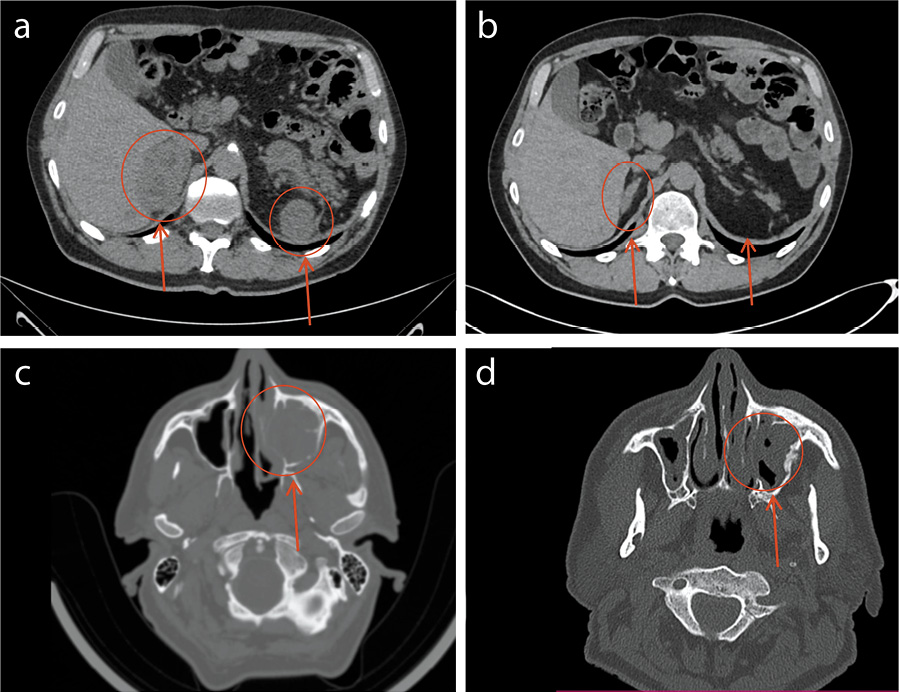

Но состояние пациента оставалось стабильным, дополнительных жалоб не предъявлял. Эффект лечения трактован как «неподтвержденное прогрессирование», лечение ниволумабом продолжено. На 4-м месяце иммунотерапии состояние пациента незначительно ухудшилось. Ухудшение состояния выражалось в появлении болей в подглазничной области слева, заложенности носа. При обследовании выявлено объемное образование в проекции левой верхнечелюстной пазухи. Выполнены биопсия образования, ангиография артерий головного мозга, эмболизация левой верхнечелюстной артерии. По данным гистологического и иммуногистохимического исследования операционного материала – метастаз почечно-клеточной карциномы в пазуху носа. В этот же период времени проведен контроль уже оцениваемых таргетных очагов, выявивший дальнейшее увеличение размеров очаговых образований в печени, проекции правого надпочечника, в проекции зоны резекции (рис. 2).

Рис. 2: а, b – увеличение таргетных очагов в печени (а – до начала иммунотерапии; b – через 4 мес иммунотерапии); c, d – увеличение таргетных очагов в проекции правого надпочечника и проекции зоны резекции (c – до начала иммунотерапии; d – через 4 мес иммунотерапии).

Несмотря на продолжающееся увеличение опухолевых очагов, единственными клиническими проявлениями заболевания являлись появившееся жалобы, связанные с болью в подглазничной области слева и заложенностью носа. С учетом того что исследование околоносовых пазух пациенту выполнялось впервые и ухудшение состояния связано только с этой локализацией опухоли, принято решение о продолжении иммунотерапии.

По данным контрольного обследования через 6 мес иммунотерапии отмечен регресс опухоли в рамках частичного ответа (рис. 3), болевой синдром в подглазничной области слева исчез без использования анальгетиков.